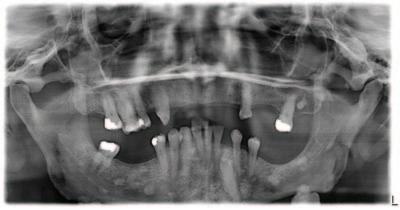

A 62-year-old man presented with a painful, firm, immobile swelling on the le border of the body of his mandible (Figure 1). Intra-orally no obvious dental pathosis was clinically visible, and his remaining le side mandibular teeth were unrestored, caries free, had no periodontal pocketing, were not tender to percussion, and were testing vital to cold testing. An orthopantomogram (OPG) was taken to assess further (Figure 2).

FIGURE 1

FIGURE 2

Quiz answers

1. Gardner syndrome.

2. Individuals who have Gardner syndrome may have hundreds or thousands of polyps in their small and large intestines, which puts them at a high risk of developing colon cancer. Oral features may include unerupted or impacted teeth, osteomas and supernumerary teeth.

3. Gardner syndrome is a rare inherited condition. It is caused by a mutation in the adenomatous polyposis coli (APC) gene. This gene is important in regulating cell growth. When the gene is faulty, cells can grow out of control,

clumping together to form abnormal growths. It is inherited in an autosomal dominant pattern.

4. Gardner syndrome may be suspected in individuals who have more than 100 polyps during colonoscopy procedures. Dentists may also notice features such as impacted teeth, osteomas and supernumerary teeth from radiographs. Genetic testing is needed for definitive diagnosis.

Questions on page 7